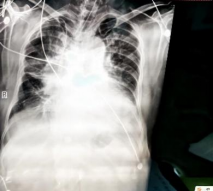

2025/11/20床旁胸片

2025/11/20复查床旁胸片:1.双肺纹理增强,模糊,双肺散在条片影,请结合临床及CT检查2.右肺门影增大,结合CT 3.心影饱满4.双侧胸腔积液,左侧为著5.双侧多发肋骨走行欠规整,结合病史 6. 气管插管后